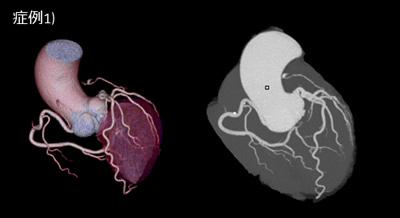

症例2) 70歳台 男性

他院でのLAD STENT治療後の状況でASOがあり冠動脈評価のためにCTを施行した。

STENT狭窄が無いことがわかりやすい。